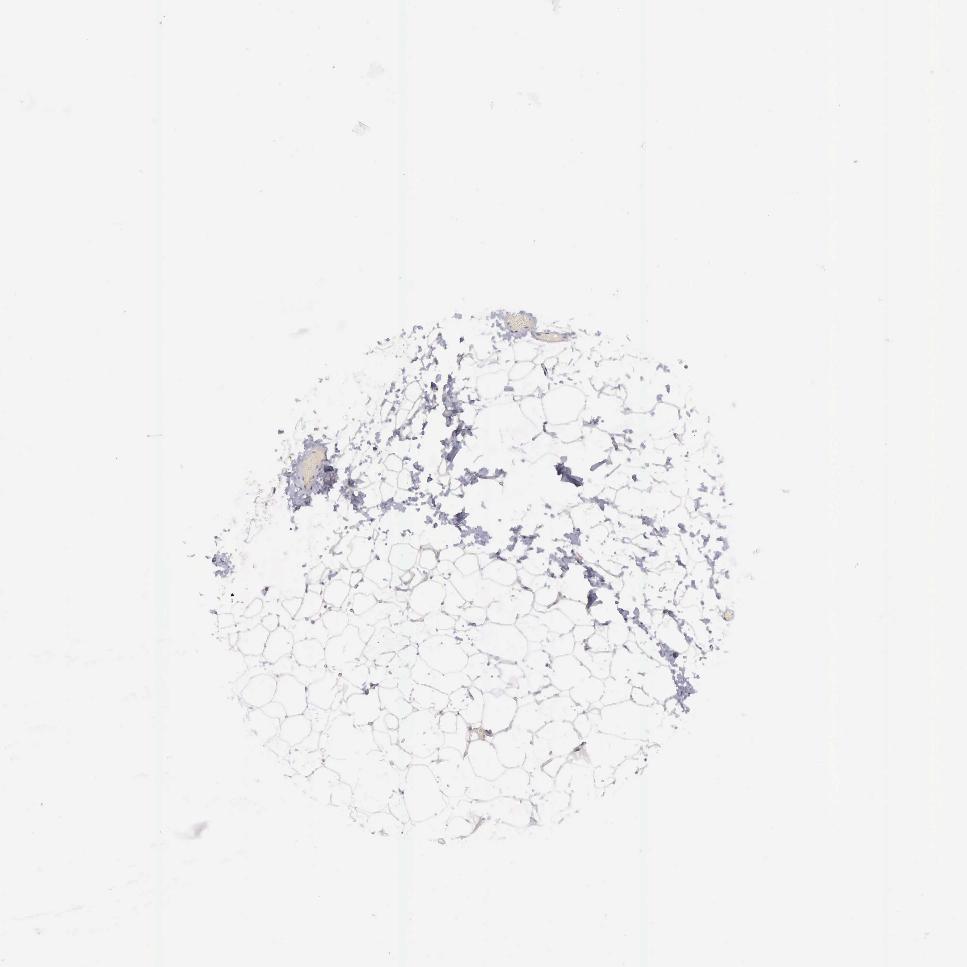

ADIPOSE TISSUE - Antibody stainingi

Antibody staining in the annotated cell types in the current human tissue is reported as not detected, low, medium, or high, based on conventional immunohistochemistry profiling in selected tissues. This score is based on the combination of the staining intensity and fraction of stained cells.

Each image is clickable and will lead to virtual microscopy that enables deeper exploration of all samples and also displays staining intensity scores, fraction scores and subcellular localization as well as patient and tissue information for each sample.

Antibody HPA028598Antibody CAB000153

Adipocytes Not detectedNot detected